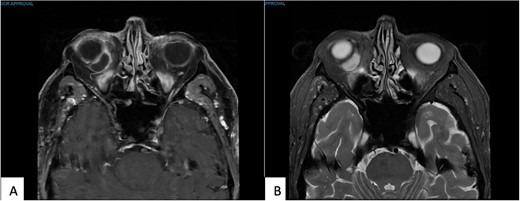

Preceding this presentation, magnetic resonance imaging (MRI) attributed his presenting features to an inflamed retroorbital congenital cystic structure, adjacent to the inferonasal aspect of the globe, accompanied by mild inflammatory changes in the surrounding orbital tissues. At the time, this was considered radiologically not infective (Fig. 1). He was afebrile, without raised inflammatory markers. Whilst pending further diagnostic opinion, a trial of oral steroids was given. He had clinically improved within the month of commencing treatment with reduced inflammation.

(A) T1 MR Orbits, and (B) T2 MR Orbits shows an intraconal mass measuring 16 × 8 × 15 mm in the inferonasal quadrant abutting the wall of the globe in the right orbit.